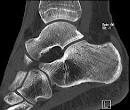

Ankle Abdomen